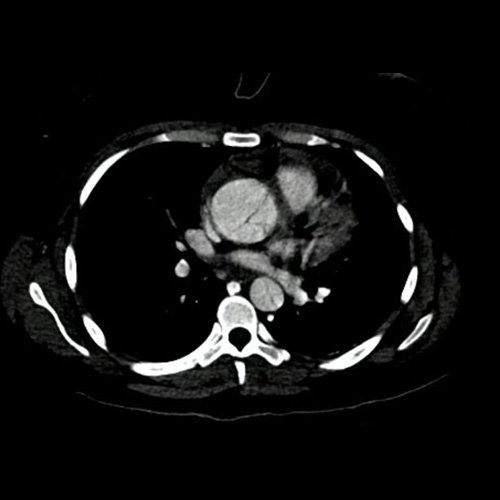

• Angio-TCMS de aorta toracoabdominal y vasos iliofemorales - pre informe (día 0): Interpretación: Se identifica un flap de disección aórtica, que se extiende desde la raíz aórtica, hasta el segmento distal de la aorta torácica descendente, asociado a dilatación aneurismática de la raíz aórtica y la aorta ascendente. No se observa disección de aorta abdominal al momento del examen. El flap de disección compromete la aorta ascendente, el arco aórtico y los tres vasos supraaórticos, extendiéndose hacia el tronco braquiocefálico derecho, con compromiso de la arteria subclavia derecha, así como también de la porción proximal de la arteria carótida primitiva izquierda y de la arteria subclavia izquierda. No impresiona compromiso de la emergencia de las arterias coronarias por esta metodología. Diámetros de la Aorta en sus diferentes porciones:  Senos de Valsalva: 40 mm.  Región media de aorta ascendente: 37 mm. Región media del cayado: 23 mm. Región media de la aorta descendente: 22 mm. A nivel de las cruras diafragmáticas: 19 mm. A nivel del origen del tronco celíaco: 18 mm. A nivel infrarrenal: 14 mm. Previo a su bifurcación iliaca: 13 mm. Hipertrofia del ventrículo izquierdo. Derrame pericárdico de 13 mm de espesor a nivel de cara anterior, de densidad promedio de 30 UH. El esófago es de calibre y trayecto normales. El mediastino está en posición central. No se observan adenomegalias mediastinales, axilares o hiliares. El árbol traqueobronquial no presenta alteraciones. Áreas de aneumatosis bibasal. No se observa derrame pleural. El hígado es de forma, tamaño y situación habituales. Su superficie es lisa, y sus bordes son agudos. El parénquima hepático presenta atenuación heterogénea, con áreas hipodensas difusas, hallazgos que podrían estar en relación con trastorno perfusional. Se observa además edema periportal. La vía biliar intra y extrahepática es de calibre conservado. La vesícula biliar es de forma, tamaño y situación normales, sin imágenes que sugieran la presencia de litiasis. Tener en cuenta que este método puede pasar por alto litiasis colesterínicas. Edema perivesicular. El bazo es de forma, tamaño y situación normales. El eje esplenoportal es de calibre y trayecto conservado, permeable. El páncreas es de características normales. El conducto de Wirsung es de calibre conservado. Las glándulas adrenales son normales. Ambos riñones son de forma, tamaño y situación habituales. Concentran y eliminan normalmente la sustancia de contraste, sin evidencia de alteraciones calicopiélicas ni ureterales. La vena cava inferior y las venas ilíacas primitivas, internas, externas y femorales son de calibre y trayecto conservados, permeables. No se observan adenomegalias intraperitoneales, retroperitoneales, ilíacas ni inguinales. No se observan alteraciones a nivel del tracto gastrointestinal. Vejiga con escasa repleción, con sonda balón en su interior. El útero es de forma, tamaño y situación conservada, sin alteraciones densitométricas, en anteversoflexión. En topografía de ambos anexos se observan colecciones líquidas de aspecto funcional que miden 23 mm a izquierda y 18 mm a derecha. Escasa cantidad de líquido libre en el fondo de saco de Douglas. Espondiloartrosis de la columna dorso-lumbar.

Angiotomografía con contraste endovenoso de aorta torácica. Corte axial.